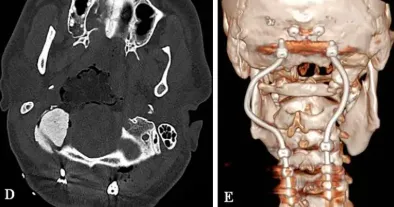

术后的效果也如福教授所料,经过PMMA材料枕髁重建的部位稳定牢固,形态恢复良好。三维CT也显示杰森C0-C3-C4-C5枕颈融合稳定,螺钉的弯曲设计也有助于后续质子治疗的开展。